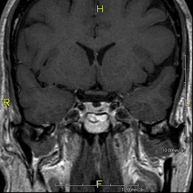

- Brain MRI (cranial)

This non-invasive diagnostic procedure uses an electromagnetic field and radio waves (from a transmitter and receiver) to acquire high-definition anatomical images of the brain. It is a radiation-free procedure. Indicated for: vascular problems, memory loss, epilepsy, headache, malformations, suspected tumour, meningitis.